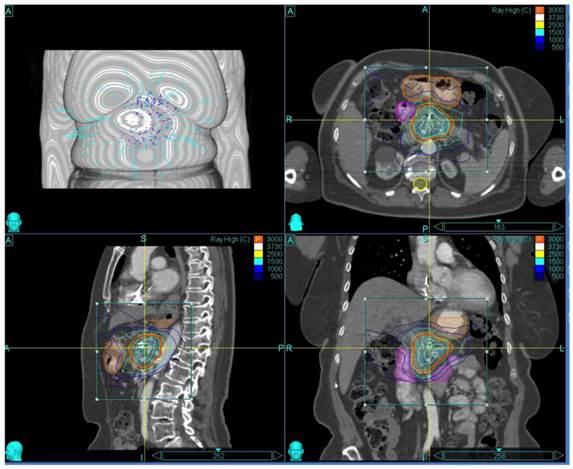

The patient and treatment characteristics are listed in Table 1. A representative treatment Plan is shown in Figure 1.

Figure 1

Representative Treatment Plan

J Cancer Image